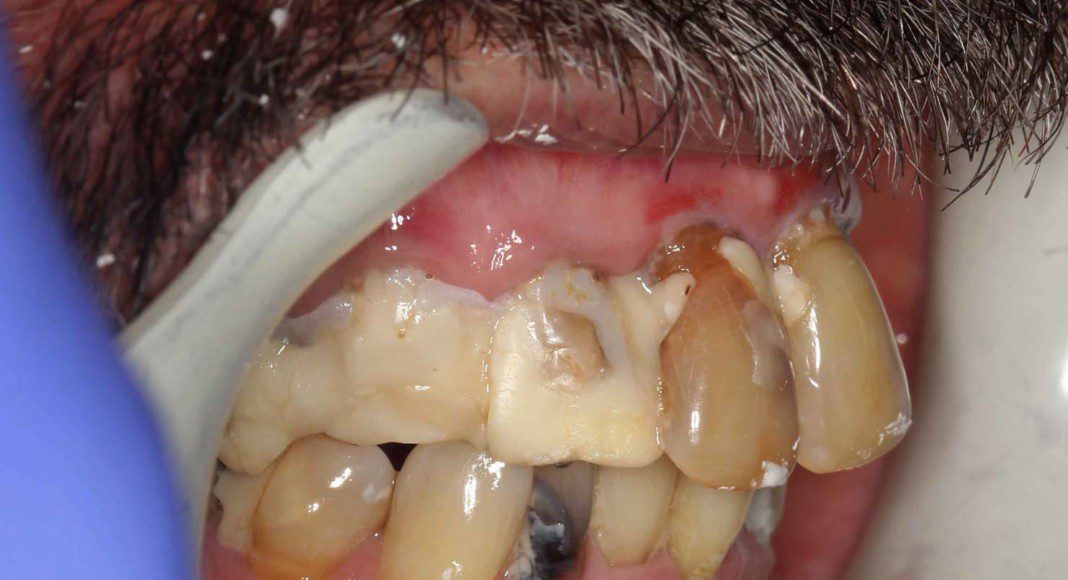

Day of surgery panoramic x-ray. Test implants were placed and adequate insertion torque was obtained (bone density and implant stability measured ≥ 25 Newton-centimeters) which qualifies multiple implants for immediate temporaries. All other teeth were extracted and a total of eight implants placed in the upper jaw (maxilla).